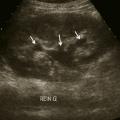

L’échographie abdominale a l’inconvénient d’être opérateur-­dépendante. Ses principales indications sont la lithiase biliaire et ses complications, des douleurs abdominales chez les patients minces et surtout chez la femme pour rechercher une pathologie gynécologique en utilisant le cas échéant des sondes endocavitaires. Ainsi, l’échographie est utile pour affirmer la lithiase biliaire et la cholécystite aiguë (fig. 1) ou objectiver une dilatation de la voie biliaire principale (VBP), rechercher une urétéro-hydronéphrose et des signes indirects en cas de colique néphrétique (fig. 2 et 3), débrouiller le diagnostic des douleurs abdomino-­pelviennes chez la femme.

L’échographie est essentielle, montrant un épaississement de la paroi vésiculaire à plus de 6 mm et la présence de calcul(s) ou « sludge » (fig. 1), sans dilatation de la voie biliaire principale (VBP). La complication principale est la péritonite et le choc septique souvent sur une gangrène de la paroi vésiculaire qui peut conduire de manière exceptionnelle vers le cholépéritoine.

L’échographie peut montrer une discrète asymétrie des cavités excrétrices rénales, voire l’obstacle lithiasique avec dilatation d’amont (fig. 2 et 3). L’uroscanner complète le bilan et localise si besoin le calcul. Outre le traitement de la cause (calcul, compression extrinsèque…), le traitement antalgique est primordial : anti-inflammatoires non stéroïdiens (AINS), paracétamol, anti­spasmodiques voire dérivés morphiniques. On procédera à la pose d’une sonde urétérale en cas d’anurie (rein unique), de fièvre sur rétention du haut appareil ou de crise hyperalgique.